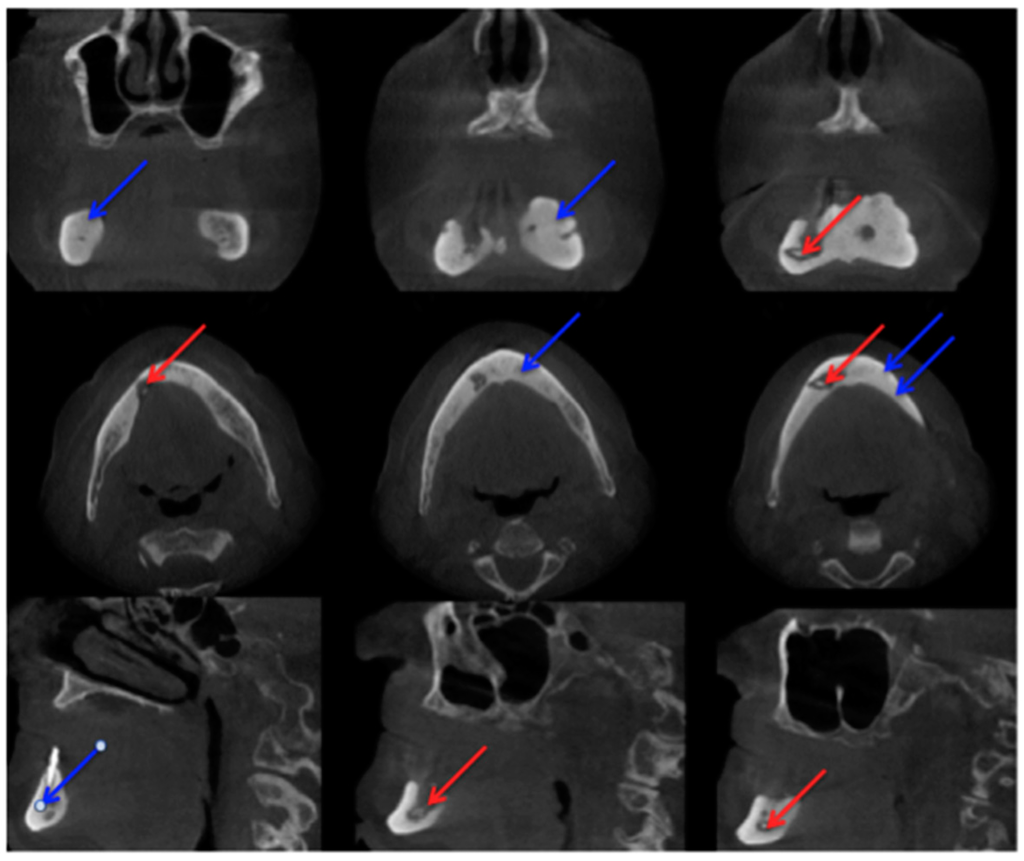

Bianchi et al. [20] assessed 32 panoramic radiographs and CT scans in detail for the following features: “structural alteration of trabecular bone, from initial change in thickness and mineral content of the trabeculae to the formation of microlacunae; cortical bone erosion; osteosclerosis; small (less than 15 mm) sequestrum; extensive (more than 15 mm) sequestrum; and presence of periosteal new bone.” They found that CT was superior to dental panoramic radiographs in detecting all the radiologic signs [20]. Cortical bone erosion and trabecular bone resorption were visible to different extents. In their readings they found that panoramic radiographs missed the correct diagnosis of sequestra in 15 cases [20]. In our example case, even a fracture could be missed if only the panoramic radiograph is assessed (Figure 3 and Figure 5).

Figure 5.

Computed tomography (Siemens, Sensation 64) Patient: 66 years old, male, secondary osteoporosis due to castration, alendronate. Red arrow points in the direction of the fracture due to the bisphosphonate necrosis. The panoramic radiograph is shown in Figure 3 and the 99Tcm-DPD SPECT and 99Tcm-DPD SPECT/CT in Figure 8 and Figure 9 respectively. AAMOS staging: stage 3.

The extended follow-up (CT scans at 3, 6, 12, 18, and 24 months) by Bedogni et al. was able to show that “CT signs of recurrent disease are apparent within 6 months after surgery and precede clinical manifestations of BRONJ” [21]. Sanna et al. stated that CT helps to differentiate between MRONJ and metastasis [33]. Elad et al. assessed 110 CT scans and stated “the mandibular canal cortex was resistant to the destructive process of the jaw, unlike in metastases” [34], but there are MRONJ cases which are still difficult to diagnose even with CT. Clinical examination is mandatory for diagnosis [35]. Farias et al. mentioned that the CT image features did not differ significantly between cases with or without exposed bone [35]. Not only are changes in bone investigated in patients with MRONJ, but thickening of the sinus maxillary mucosa is also examined [20]. A study by Gallego et al. were able to show patients with MRONJ had greater probability of presenting sinus mucosal thickening in comparison to a healthy group. They used a thickening of >3 mm as their measurement value. In their assessment, they found that the thickening was present more in patients with “advanced-stage disease” [36]. In their study, Hutchinson et al. concentrated on radiographic characteristics in patients with “stage 0 disease” [37]. Ten patients met the criteria for “stage 0”. They included 1× panoramic image, 2× CBCT scans, and 9 CT scans. The authors reported “Diffuse osteosclerosis in clinically symptomatic areas, characterised most with extension beyond the involved site, density confluence of cortical and cancellous bone, prominence of the inferior alveolar nerve canal, markedly thickened and sclerotic lamina dura, uniform periradicular radiolucencies, cortical disruption, lack of bone fill after extraction, and a persisting alveolar socket.” [37]. Hamada et al. [38] reported “A simple evaluation method for early detection of bisphosphonate-related osteonecrosis of the mandible using computed tomography”. They found no significant differences between means of administration (intravenous or oral) and length in regard to “cancellous bone CT radiodensity value, cortical bone CT radiodensity value, and cortical bone width.” [38]. Otherwise they found differences between the MRONJ group and a control group regarding cortical bone width. In cancellous bone, CT radiodensity values even varied “among the BRONJ area, the non-BRONJ area, and the control groups” [38]. A limitation of this study, which should be mentioned, was the size of the MRONJ group. A total of 20 patients were included; only 4 patients received bisphosphonates orally. Of these 4 patients, 3 patients received risedronate and 1 patient received alendronate [38], therefore although it provides some valuable information, a larger sample size would be desirable. The patient group assessed in the article by Wutzl et al. included 17 patients. All of them presented sclerotic zones. In 9 of these patients MRI and scintigraphy were performed. They stated that, “sclerotic changes on the CT scan appeared hypointense on MRI.” [39]. Bisdas et al. found “sclerotic regions in the jaws with or without periosteal bone proliferation.” [40]. A large multicentre study (“MISSION”) assessed in detail 799 patients suffering from MRONJ in regard to staging/CT. From their point of view, future staging systems should consider both clinical signs and CT findings [41].